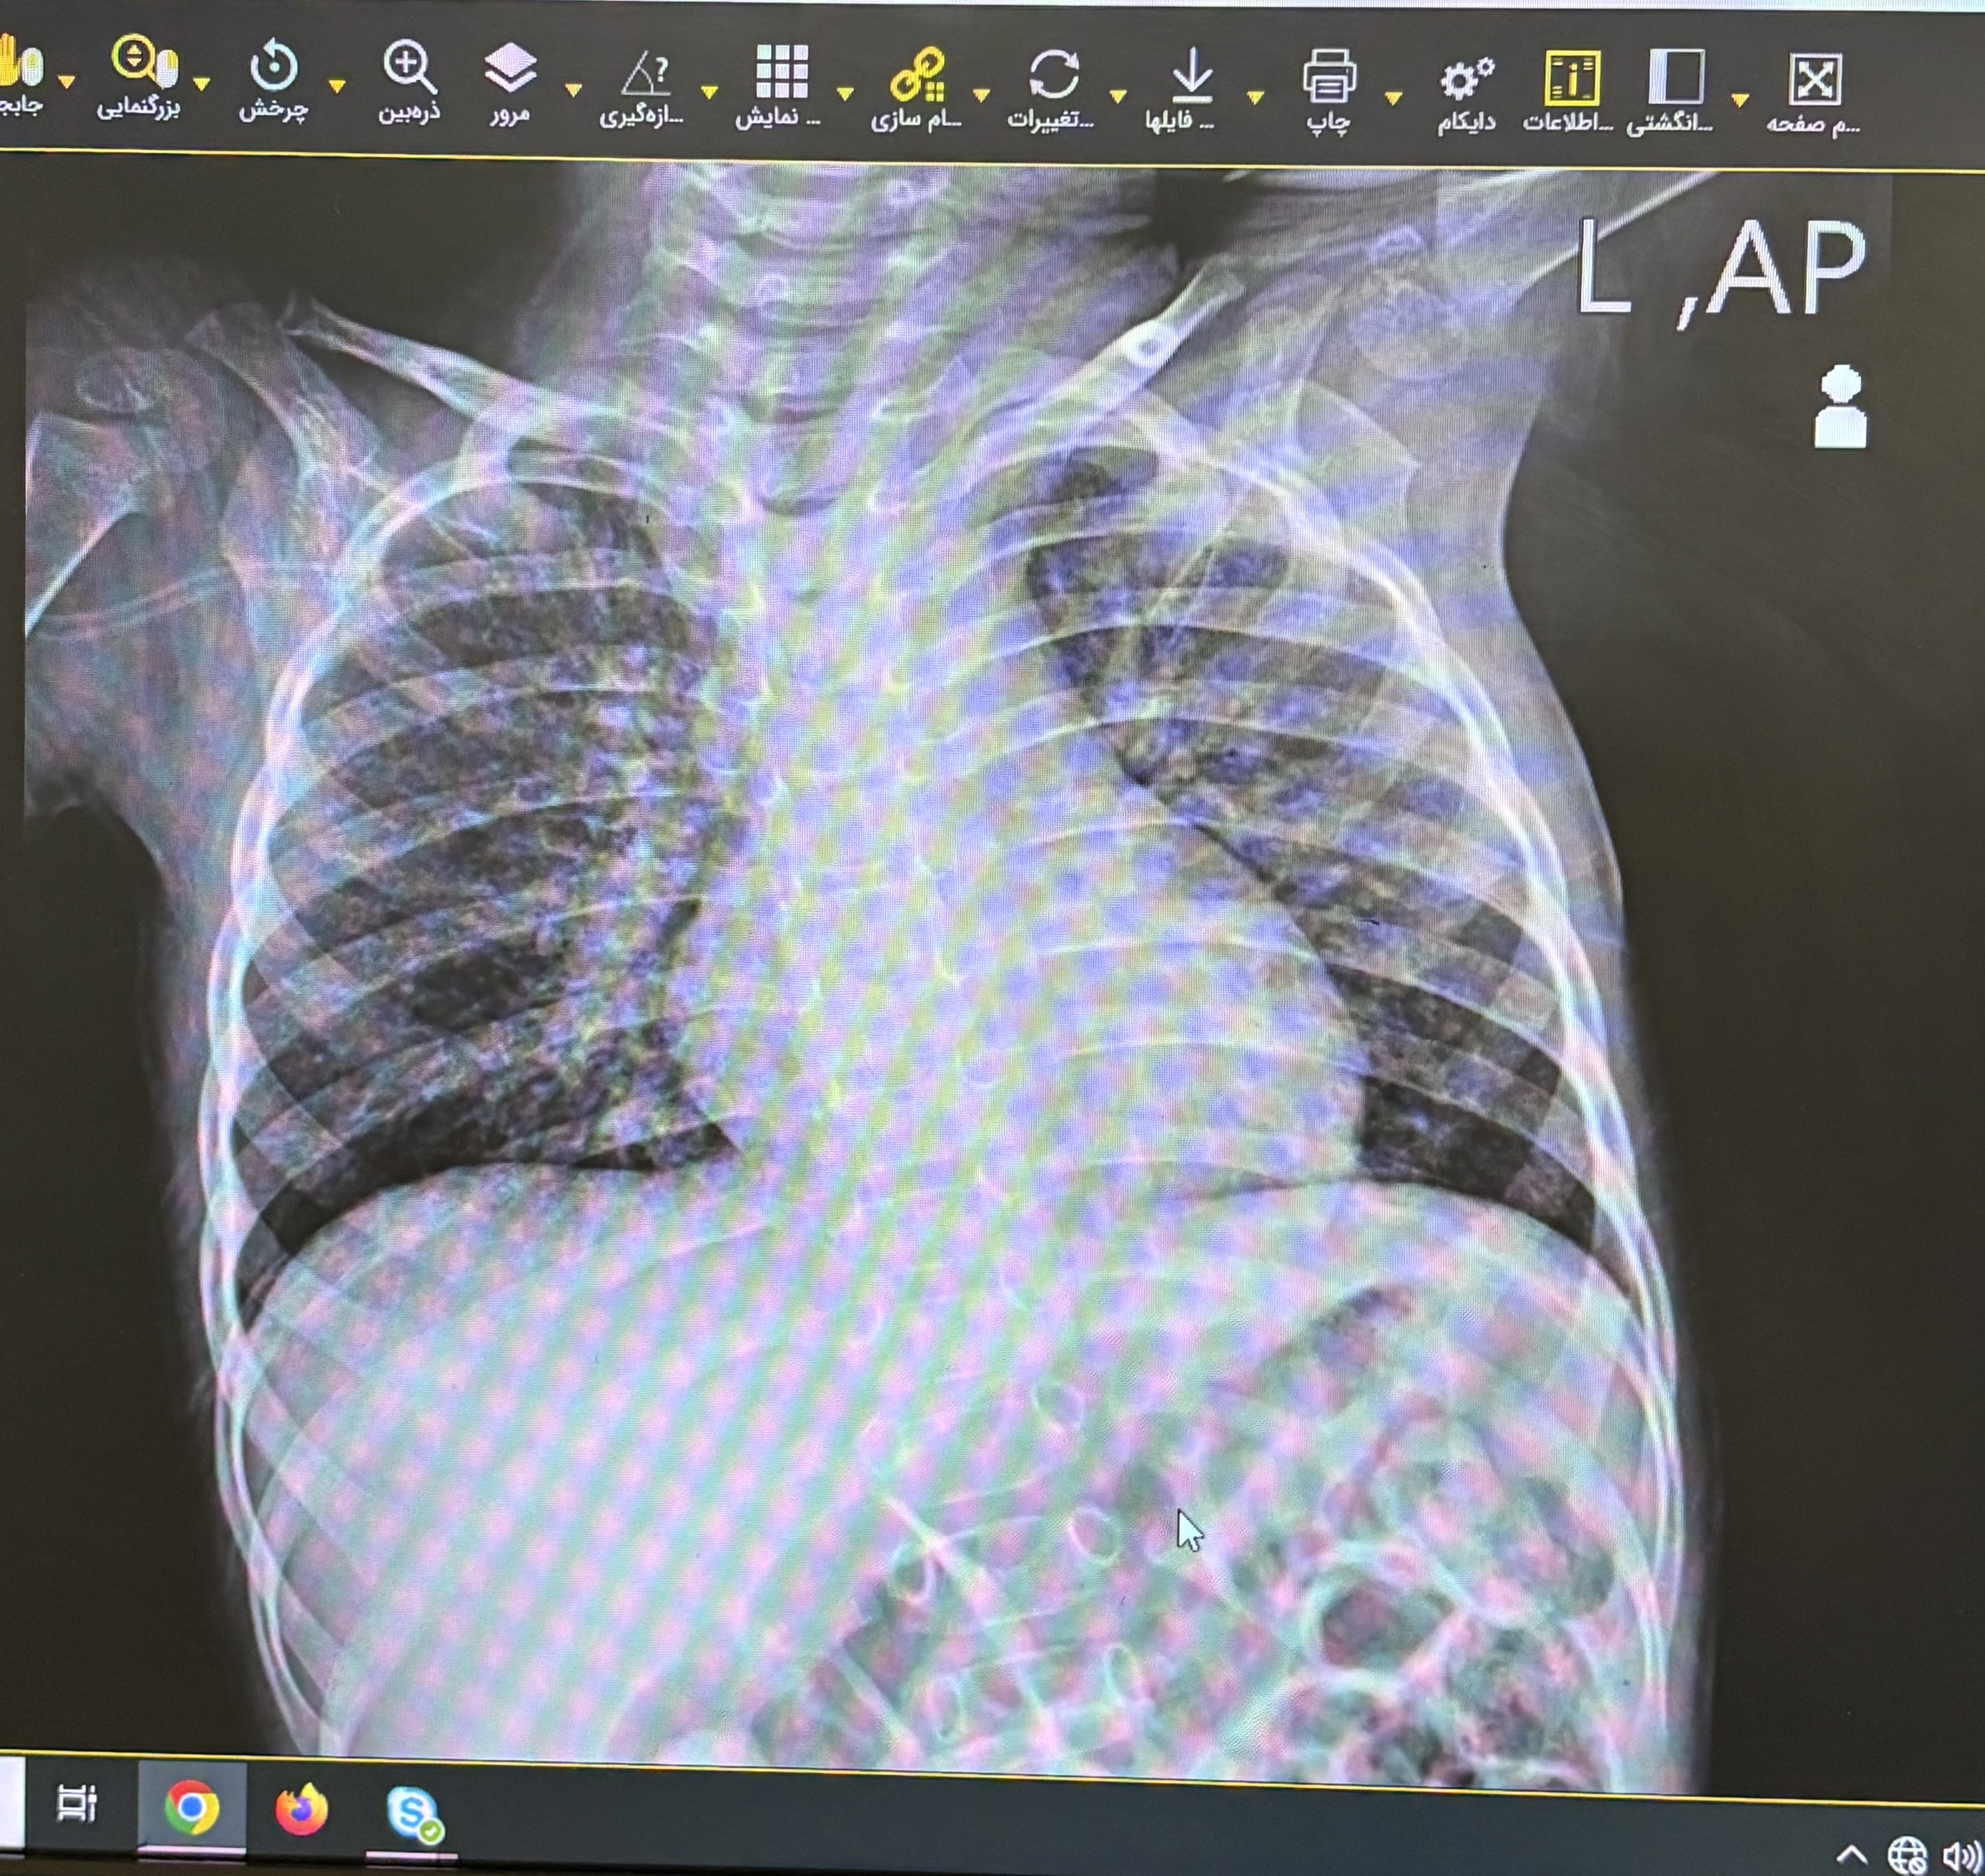

دیشب یک نوبت تب داشته که به استامینوفن جواب داده و یک نوبت استفراع به دنبال سرفه هم داشته صبح امروز هم یک نوبت تب را ذکر میکنند و در سمع ریه، کراکل دوطرفه شنیده میشد

pneumunia

bronchitis

atypical pneumonia

bacterial bronchopneumonia

aspiration pneumonia/bronchitis

covid-19/influenza

Pneumonia

X-Ray: